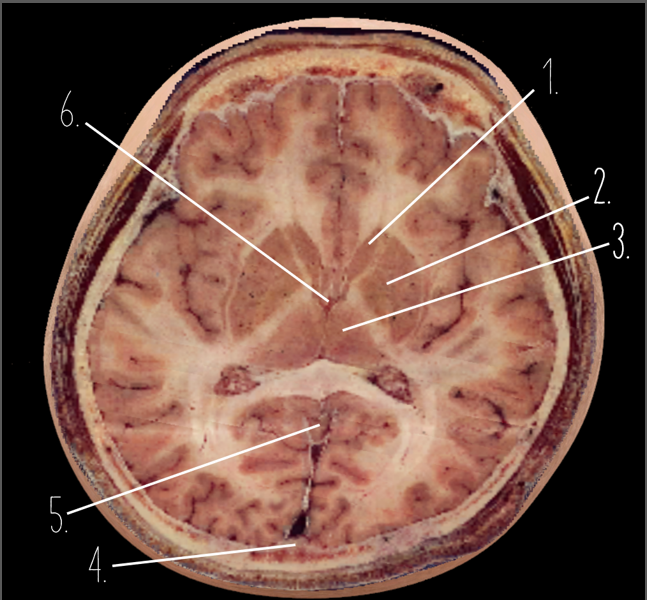

1

Frontal Bone

2

Frontal Lobe

3?

Falx Cerebri

4?

Gray Matter

5?

White Matter

6?

Sulcus